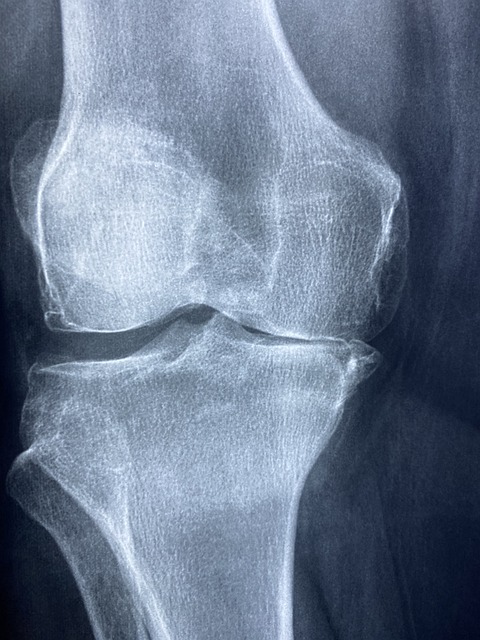

MBP(Milk Basic Protein)는 우유에서 극소량 추출되는 고기능 단백질로, 식약처에서 골밀도 유지 기능성을 인정받은 성분입니다. MBP는 뼈의 세포 활동 자체에 영향을 주는 기능성 원료라는 점에서 칼슘제와는 차별화됩니다.

- 조골세포(뼈 생성 세포)를 활성화하여 새로운 뼈가 형성되도록 돕고

- 파골세포(뼈 파괴 세포)의 활동을 억제하여 뼈 손실을 줄여줍니다

1. 골밀도 유지 및 골다공증 예방

MBP를 일정 기간 섭취하면 골밀도가 유지되거나 향상되는 결과가 관찰됩니다. 폐경기 여성이나 50대 이후 남성에게 특히 유용합니다.